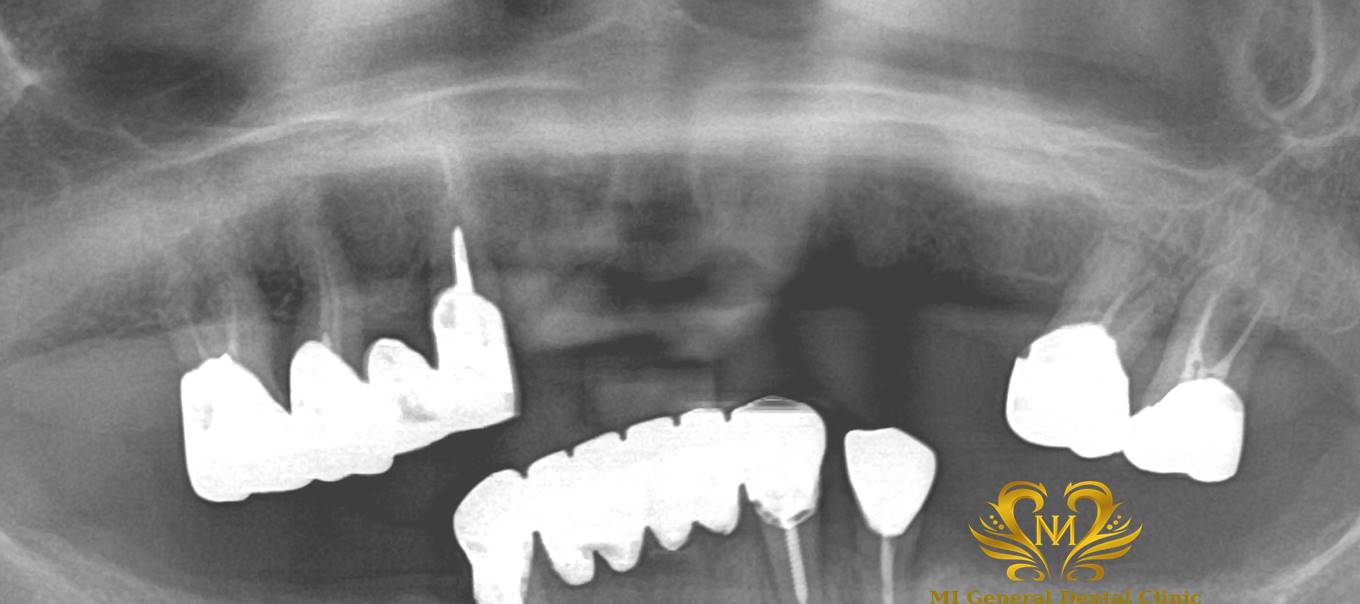

治療後

噛めるようになる。(咬合回復)

見た目が良い。(審美回復)

笑顔に自信が持てる。

外科治療が必要。自費治療。治療期間が長い。腫れ痛みが出ることがある。物が詰まりやすくなることがある。歯がない時より噛めるため、顎関節症状が出ることがある。